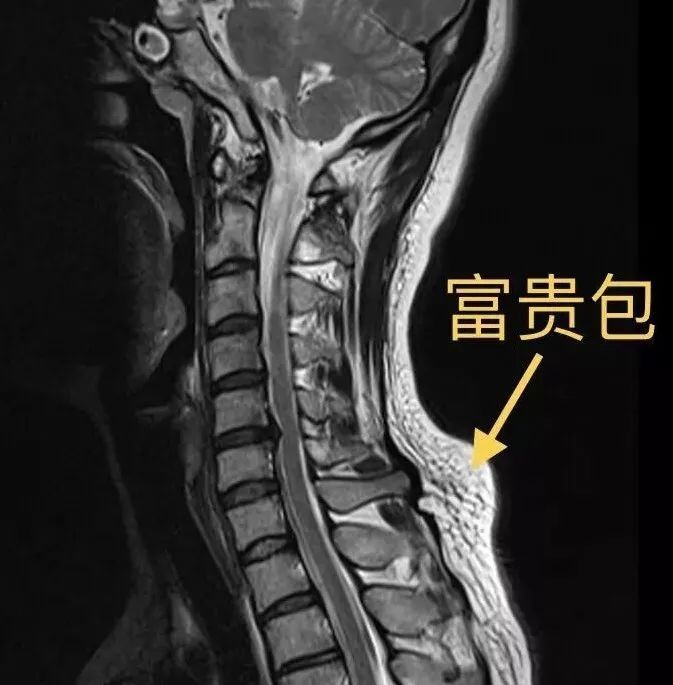

在第七颈椎隆突的位置,因为它比较高,在长期干体力活,如抬,扛东西

图片尺寸673x685